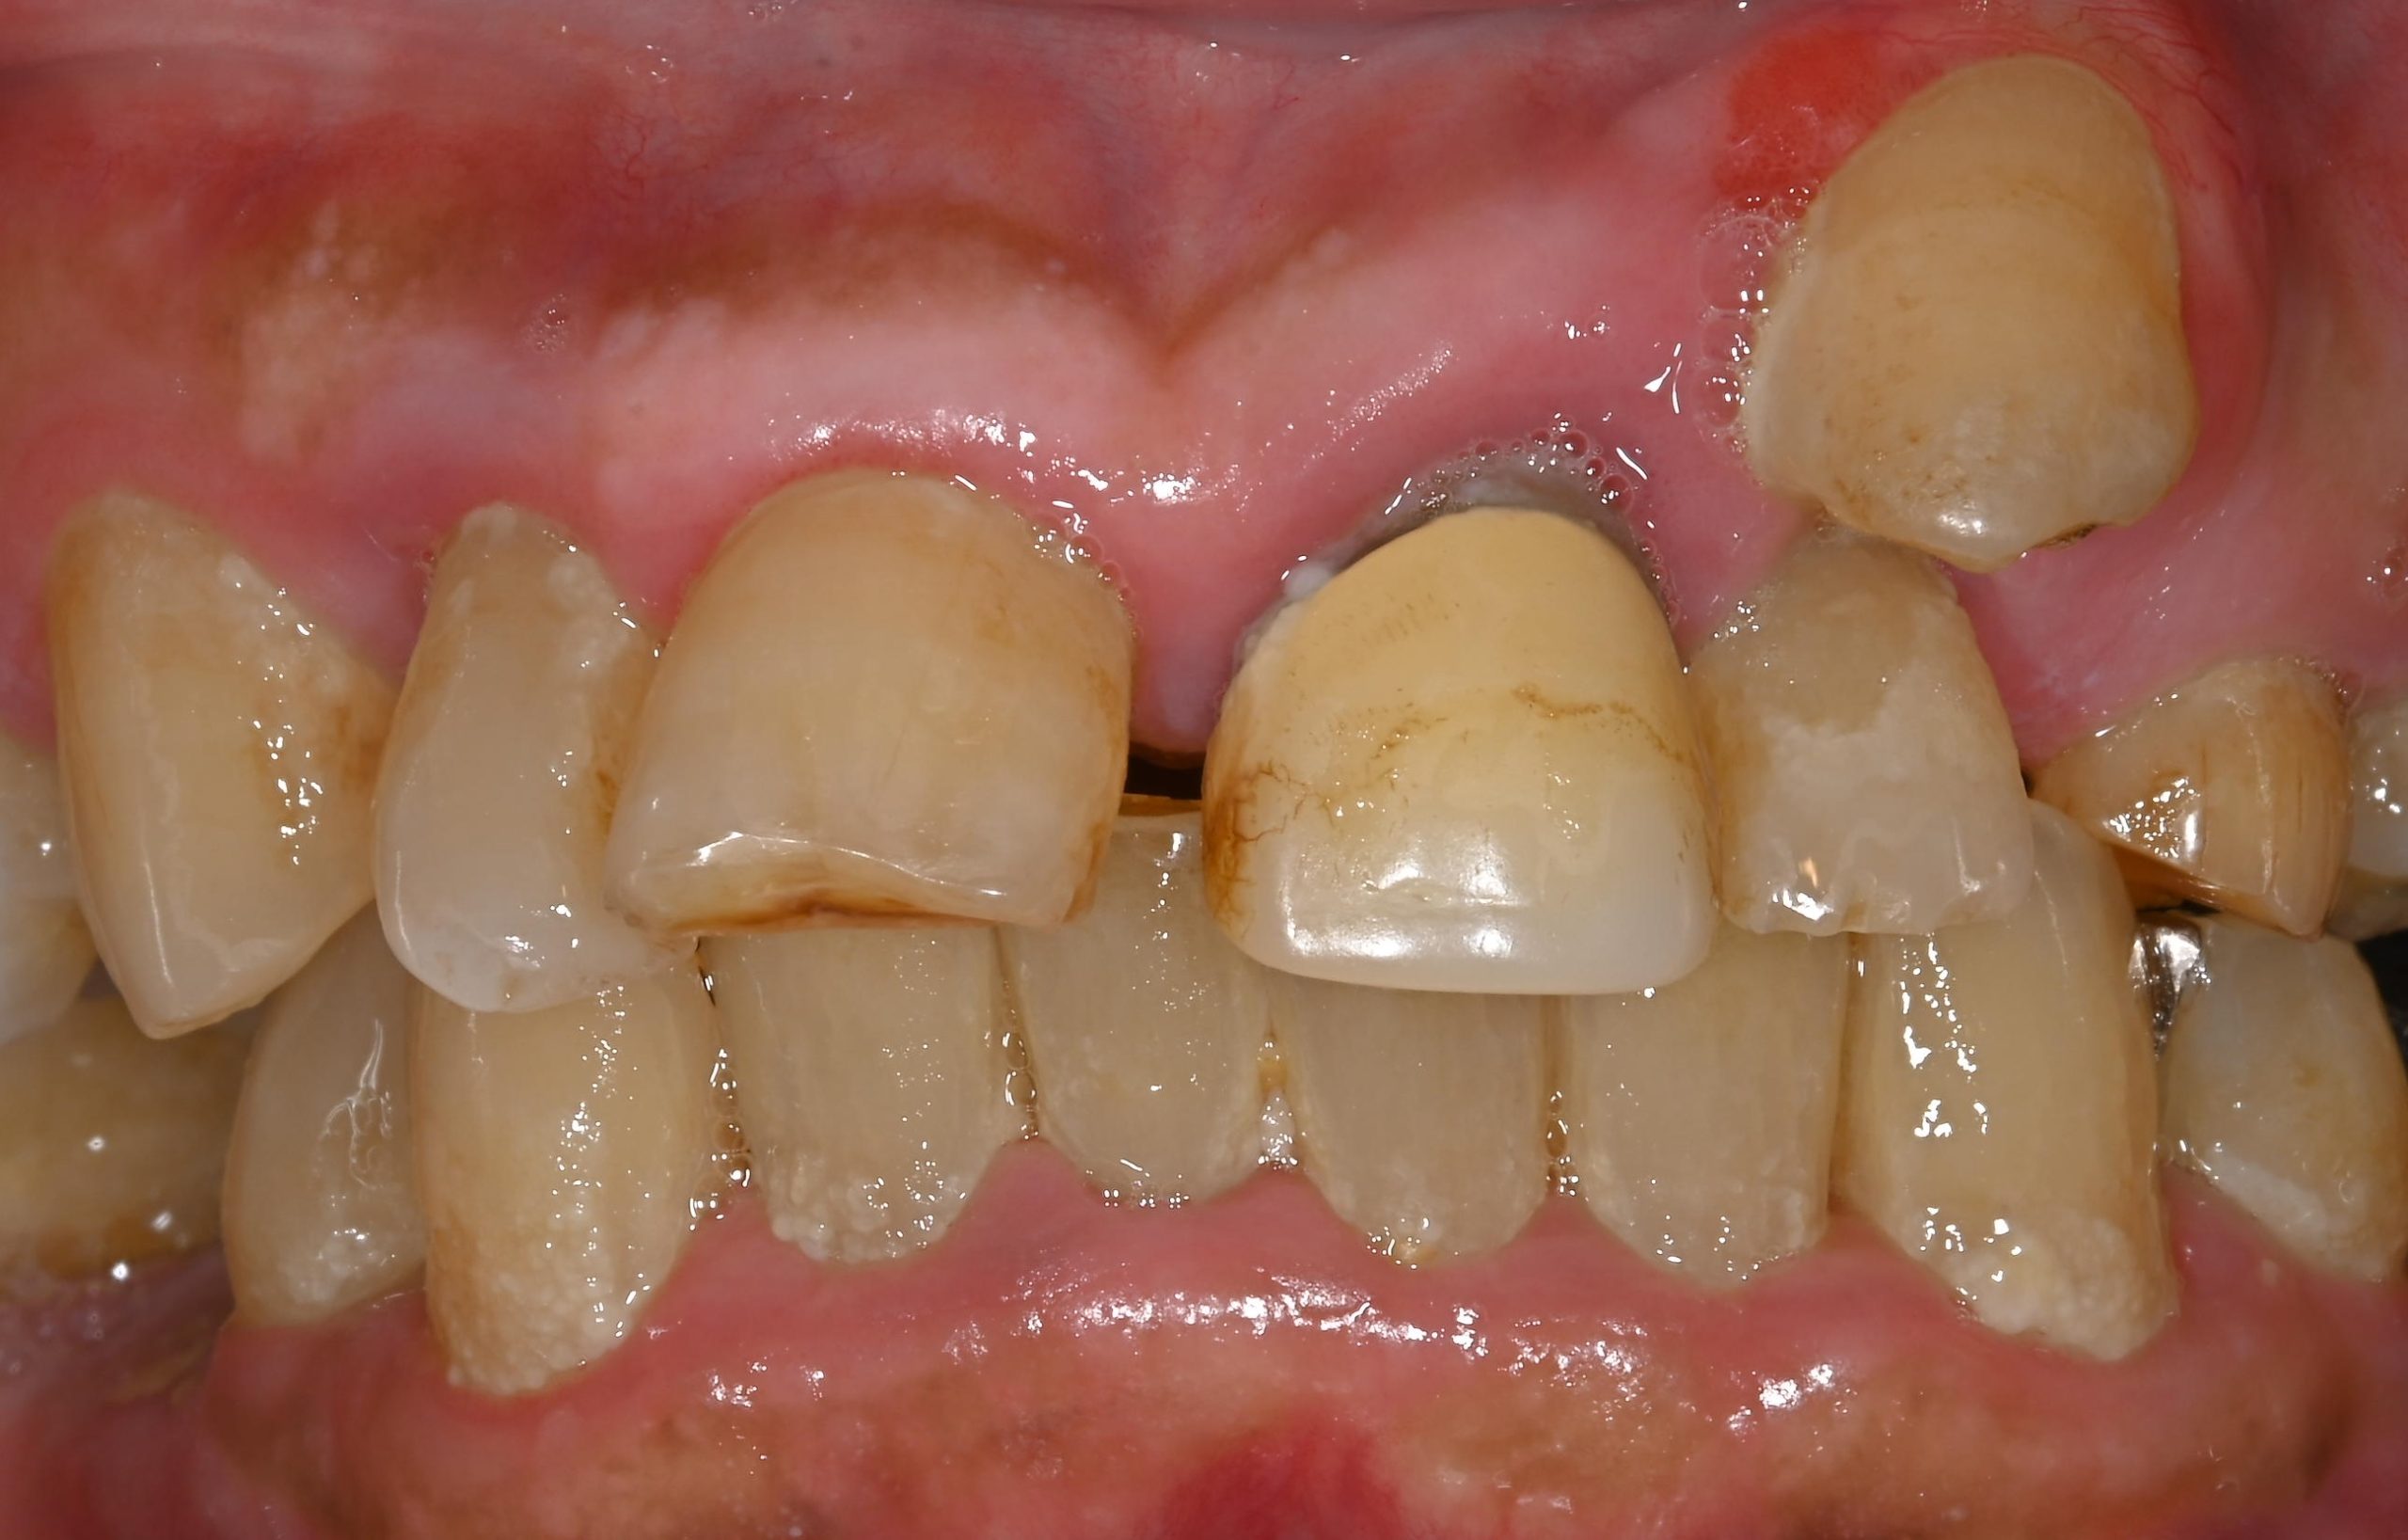

“実際の実施例1”

この患者様は、口腔内全体において重度の歯周病が生じており、歯磨き指導、クリーニング、Flap手術等を行ったが、歯周ポケットが深すぎるため

ブルーラジカル適用症例と診断し、施術を行いました。

(実施前)

施術前のレントゲンと口腔内写真です。施術前にプラークの除去を行ってから、施術します。